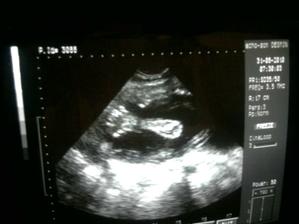

Náš anjelik🙂